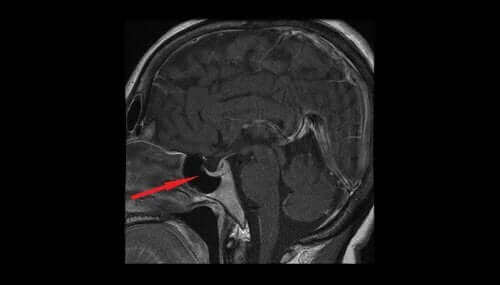

보통 시력 검사와 CT, 뇌 MRI 검사로 진단을 한다.